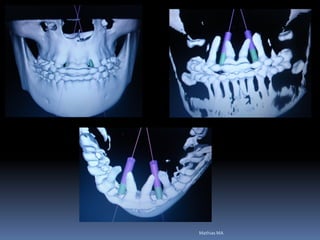

Exames Imaginológicos

Radiografias periapicais, telerradiografias e

panorâmicas;

Tomografias computadorizadas

Softwares de imagens 3D

Guia radiográfico

-posição ótima do implante com marcadores

radiopacos

•Guta percha

•Esferas e tubos metálicos

•Fios e lâminas metálicas

•Lâmina chumbo do RX

•Dentes de sulfato de bário

•Facilita perfuração, paralelismo e distribuição dos

implantes

•Elimina a medição entre implantes

•Permite alternar as possibilidades de instalação

•Vácuo- press ou própria prótese do paciente

duplicada com acrílico transparente